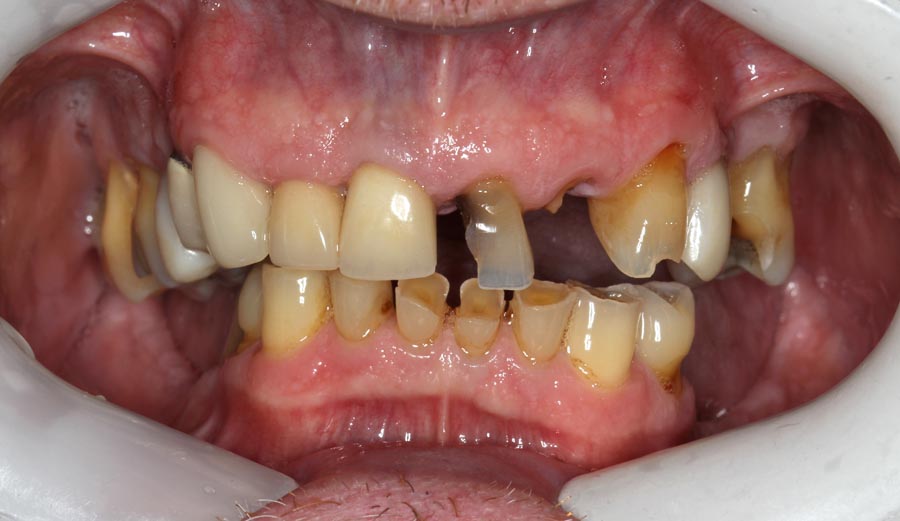

After many years of postponing, the time had come for this patient to fix his teeth. He elected to start on the upper and move to the lower one year later.

The lower teeth were bonded with composite resin to improve aesthetics and function during the year he is waiting to do his lower.